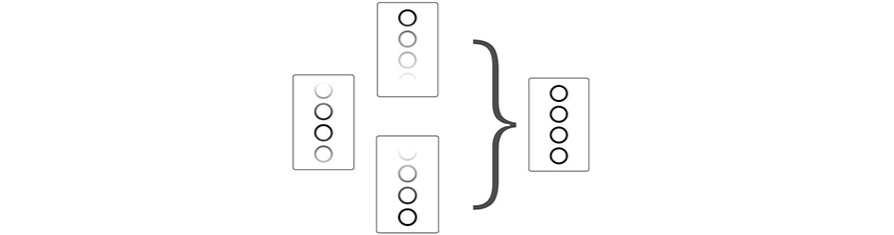

FCI (Obrazowanie wielocz?stotliwo?ciowe)

Funkcja ta pozwala na ??czenie r├│?nych cz?stotliwo?ci, aby stworzy? najwi?ksz? mo?liw? jednolito?? w ca?ym polu obrazu, zapewniaj?c lepsz? penetracj?, zw?aszcza w przypadku skan├│w wysokiej cz?stotliwo?ci.